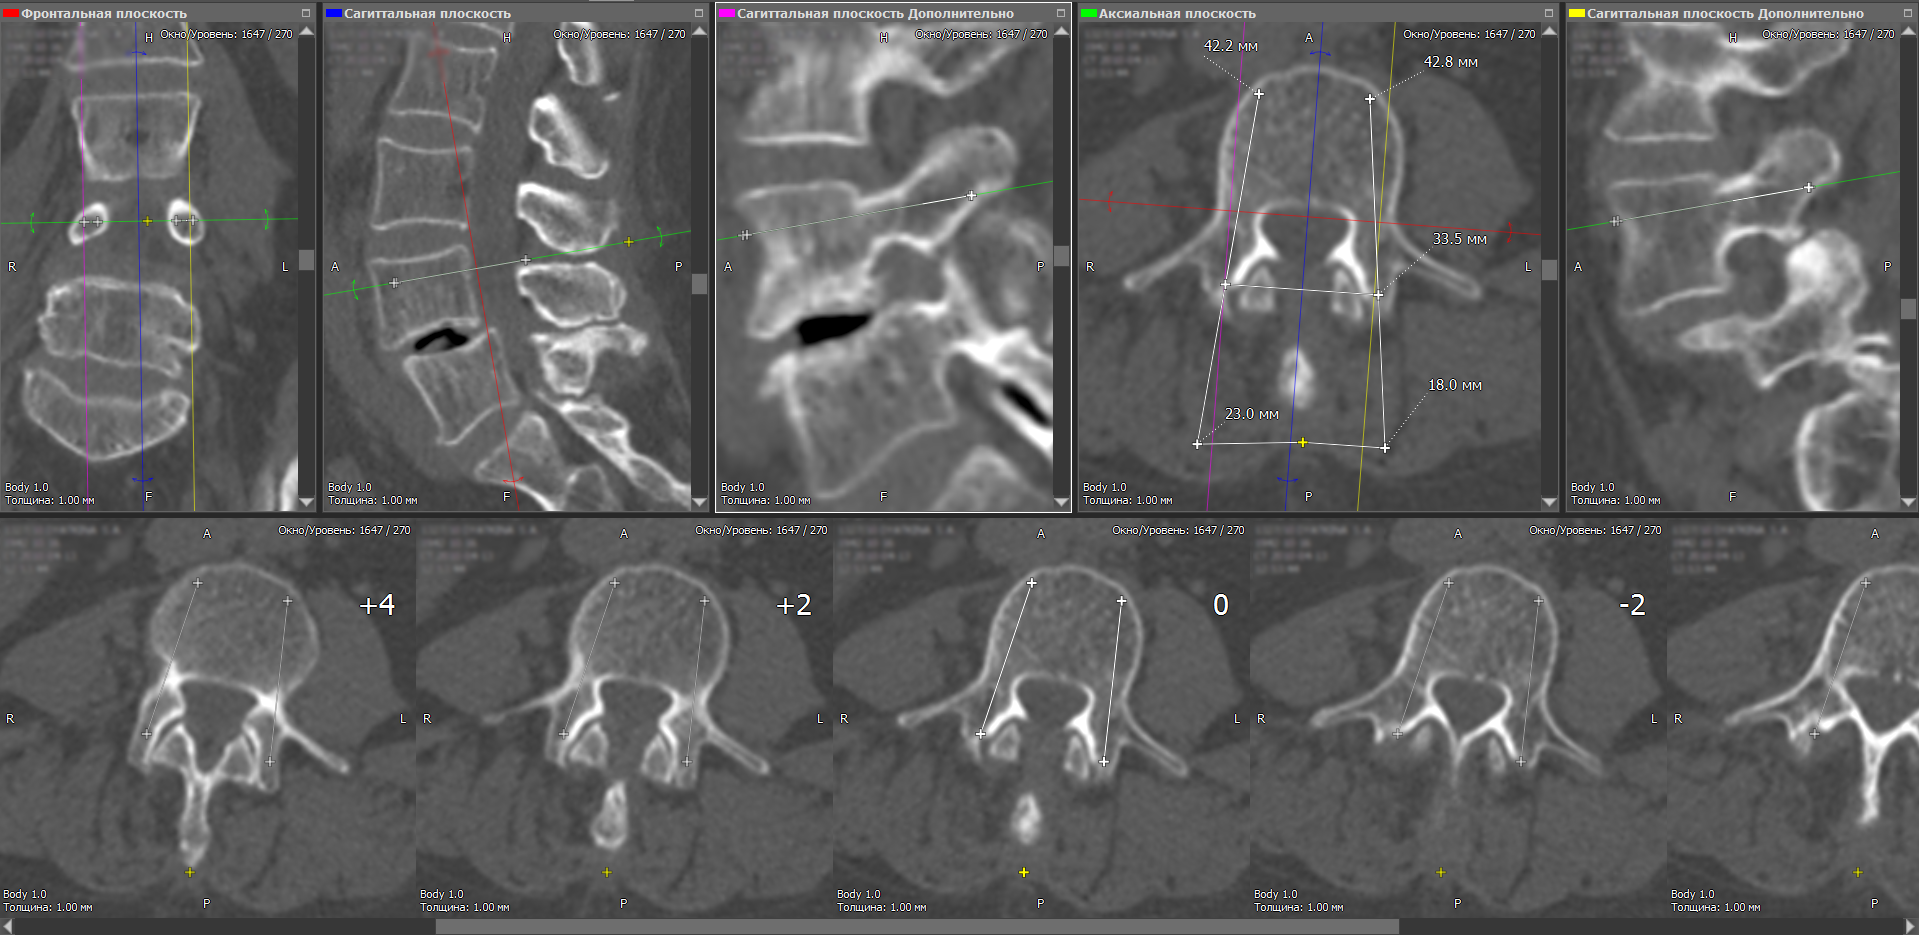

На сегодняшний день общепринятым стандартом для хранения, передачи и визуализации медицинских исследований является DICOM. С такими DICOM-данными как раз и работает наша программа. Полученные в результате КТ-обследования снимки, как правило, располагаются в аксиальной плоскости параллельно друг другу. Однако врачу в целях предоперационного контроля также важно видеть общую картину особенностей позвоночника и в других плоскостях. Для решения этой задачи используется мультипланарная реконструкция (МПР) — специальная обработка исходных данных, в ходе которой можно получать изображения в сагиттальной, фронтальной или любой произвольной плоскости.

В ходе планирования операции врач выбирает проблемный позвонок и подбирает срез в аксиальной плоскости. Также отображается дополнительно срез во фронтальной плоскости и трёх сагиттальных. Кроме того, для более детальной оценки, коррекции точек и траектории введения винтов делается набор из девяти срезов в горизонтальной плоскости с интервалом 2 мм по вертикали. Такая методика помогает всесторонне учесть анатомические особенности конкретного позвонка, чтобы исключить хирургические ошибки во время проведения операции.

Далее пользователь прочерчивает на проблемном позвонке линии траектории введения винтов AC и DF. Точки B и E – это точки ввода винтов в позвонок, а получившиеся отрезки A-B и D-E определяют их будущее положение. Во всех плоскостях отображается проекция винтов, что позволяет дополнительно скорректировать траектории их введения, которые в одной плоскости могут быть оптимальными, но в других – оказаться нежелательными или даже опасными.

Определившись с положением обоих винтов, врач размечает на снимке точку H на остистом отростке, которая нужна для определения точек C и F. Программа автоматически определяет длины нужных отрезков, которые выводятся в миллиметрах. Зная точки введения винтов (B и E), а также нужные расстояния от остистого отростка (отрезки C-H и H-F), врач во время операции может определить траектории, по которым необходимо сверлить штифт-канал, чтобы установить винты в нужном положении.

Выполнив в ходе мультипланарной реконструкции коррекцию с учётом трёхмерности позвонка, врач получает разметочные карты предстоящей операции, которые можно распечатать на обычном принтере. Таким образом, непосредственно в операционную хирург попадает с подробным планом, что и как необходимо делать.

Измерение расстояния между инструментом для формирования штифт-канала и верхушкой остистого отростка для контроля угла вхождения в аксиальной плоскости